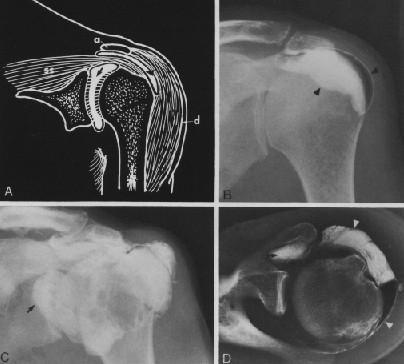

RESONANCIA MAGNETICA

Resonancia magnética

Corte sagital

Resonancia magnética Corte axial

Corte coronal